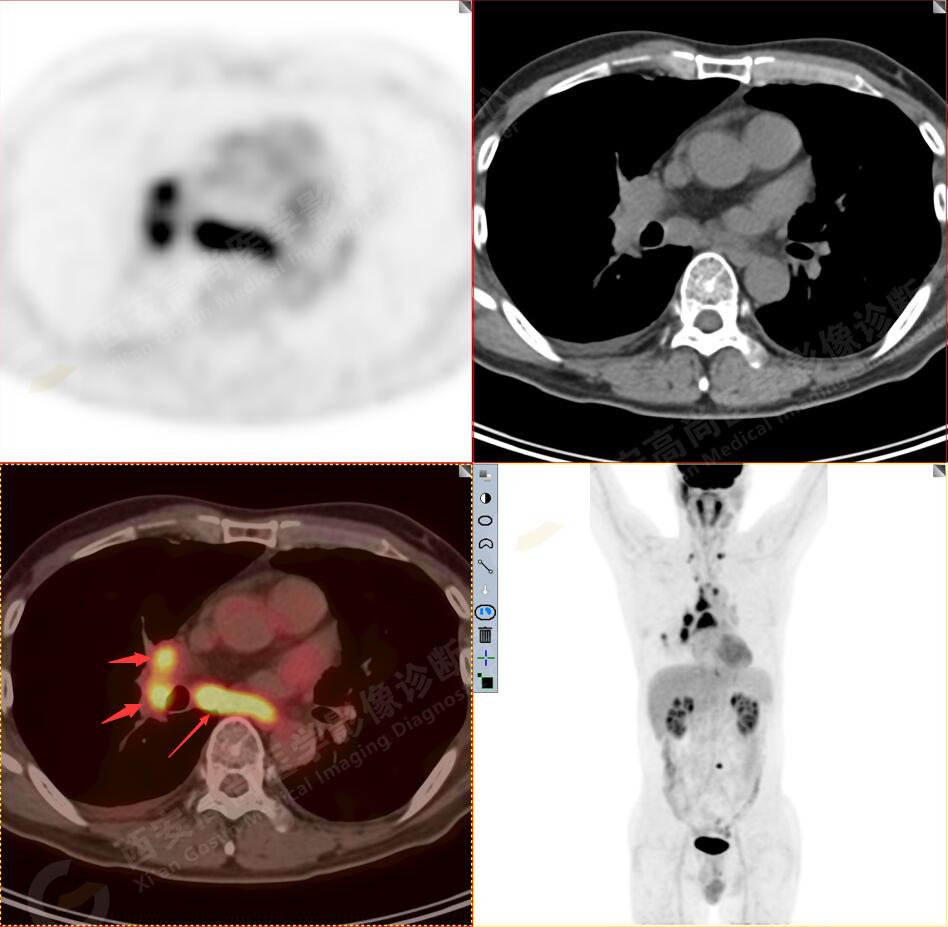

1.以下為肺內原發(fā)灶

1.右肺下葉后基底段軟組織結節(jié)(約1.5cm×1.2cm),與相鄰后胸膜分界不清,呈FDG代謝異常增高,結合病理,符合肺腺癌伴鄰近胸膜侵犯。

3.右側肺門、縱隔(1L、1R、3A、4、6、7組)及雙側鎖骨上多發(fā)腫大淋巴結,呈不同程度FDG代謝異常增高,考慮為淋巴結轉移。